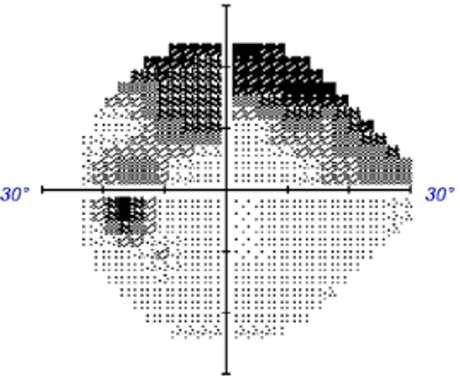

• Case 4: Peripheral field constriction

A 75 year old Caucasian male who reports good general health and a family history of glaucoma in his mother. This case will focus on his right eye. His intraocular pressure is 19mmHg in the context of average central corneal thickness (558µm).

24-2 SITA Faster visual fields